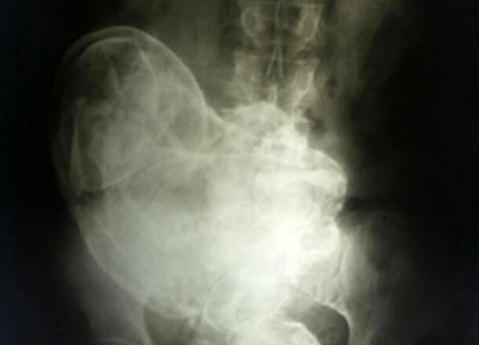

V maternici 84-letne Brazilke je odkril okamenela plod 44 let. To se je zgodilo, ko zaradi neznosnih trebušna bolečina se je ženska posvetovala z zdravnikom, ki jo je naredil Rentgenski Na sliki so videli okameneli zarodek. Ta pojav prejela v medicinsko uporabo ime litopedion. Litopedion – okameneli maternični plod, ki je umrl v maternici ali trebuhu votlina, ki je nato podvržena kalcifikaciji. Redko je pojav, ki se pojavi predvsem, ko plod med tem umre zunajmaternična nosečnost. Ker ni naravnega način, kako se znebiti takega ploda, ga telo izpostavi kalcifikacije, da se prepreči propadanje plodovega tkiva pred škodo telo nosilca. Zdravniki, ki so pregledali žensko, so zaključili da je plod umrl v 28. tednu nosečnosti. Kljub temu od operacije bolnik ga ni hotel odstraniti. Maroški primer Ta pojav je zelo redek, zato so ponavadi primeri njegovega pojavljanja posneli zgodovinarji. Ta je opisana leta 2012. Rezident majhna vasica, ki se nahaja v bližini Casablance, Maroko, mati treh otrok Zahre Abutalib zadnjič zanosila pri 26 letih. Devet mesecev brejosti plod je minil brez zapletov. Vendar je v bolnišnici postala priča smrt bolniške sostanovalke, mlade matere, ki umrl na operacijski mizi zaradi carskega reza. Ne ji je uspelo rešiti otroka. Bojilo se, da se takšna usoda lahko zgodi pričakujte, da je njena, navdušena Zahra, ki je zbirala stvari, pobegnila bolnišnice, ki se odločijo roditi doma. V naslednjih nekaj dni strašno trpela zaradi porodnih bolečin, pa vendar dolgo pričakovanih otrok nikoli ni prišel na svet. Kmalu se je povsem ustavil premakniti se v maternici in ženska se je odločila, da je otrok “zaspal”. Zahra dobro spomnil lokalni mit o “spečem otroku.” Domnevno, če ne rodi ga, potem bo vse življenje branil čast svoje matere. Zato ne še posebej skrbelo je za njeno stanje, zlasti ker so bile kontrakcije ni več ponovljeno. To je trajalo štirideset šest let, dokler pred kratkim, že pri 75. letih, se bolečina ni nenadoma vrnila. Zahra obrnili na zdravnike. Ultrazvočni pregled v mestni bolnišnici Rabat je pokazal prisotnost tuje ženske v trebuhu teles, katerih izvora zdravniki niso znali pojasniti. Bil je opravili temeljitejši pregled telesa, glede na rezultate za katero so strokovnjaki zaključili, da je trdna masa v telesu Zahra ni nič drugega kot okameneli sadež ženskega telesa čudežno zmotili organ in zato že dolgo ne dojemajo kot tuje telo. Operacija je trajala štiri ure. Na koncu je skupina zdravnikov pod vodstvom dr. Taibija Kuazzanija uspelo je iz ženskega telesa izvleči plod, ki tehta nekaj več kot dva kilogramov in ima dolžino 42 centimetrov. Torej, po skoraj pol stoletja se je Zahrov dojenček končno rodil

Fotografija iz odprtih virov Lithopedion nastaja v telesu ženske v primeru smrti ploda, običajno po ektopiki nosečnost, čeprav obstajajo primeri njegovega nastanka v maternici. Materino telo mrtvega otroka dojema kot tuje telo, plod se zaradi zaščitne reakcije mumificira. Najprej podroben opis takega primera sega v leto 1582, ko je določen Odkril je francoski zdravnik ob obdukciji 68-letne ženske okameneli sadež, ki je v maternici matere ostal 40 let. Vseživljenjska nosečnost Glede na medicinsko statistiko “kamniti otroci” lahko ostanejo znotraj človeka, dokler dolgo časa. In 46 let nikakor ni meja. Torej, januarja 2009 v v bolnišnici v kitajskem mestu Huangiaotang se je obrnil 92-letni domačin stanovalca Huang Yuijun, ki se je pritožil nad zelo hudimi bolečinami v želodec. Kakšno je bilo presenečenje zdravnikov, ko so to ugotovili starejša ženska … noseča! Poleg tega dolgo noseča – 60 let! Njena neverjetna zgodba se je po poročanju The Sunja začela nazaj leta 1948. Nato so zdravniki Huang povedali, da je plod pred tem umrl rojstvo v maternici. Če ga želite odstraniti, je bila potrebna operacija za ki so zdravniki zahtevali znesek v lokalni valuti, ki ustreza 150 dolarjev. Slišal cene, se je Huang preprosto obrnil in odšel. “Tole je Denarja je bilo takrat, pravi ženska, več kot vsi člani moje družine so zaslužili v nekaj letih. Zato i Nisem naredil ničesar in se odločil, da ne bom upošteval zdravniške diagnoze. ” “Ignoriranje” je trajalo več desetletij, dokler je pokojnik v maternica, otrok se ni več spomnil. “Nisem mogel verjeti svojim na lastne oči, ko je ugotovil, da je v maternici Yuijun otrok, “pravi dr. Liu An Bin iz bolnišnice Gwingsheng. – za moja 40 let prakse zdravnika ni nič več Nisem še videl nič čudnega ali presenetljivega. ” Bolnišnica za porodništvo in ginekologijo Xu Xiang Ming doda: “Običajno se v notranjosti zlomi mrtvi plod. Toda v tem primeru imamo opravka redek dogodek. Še vedno ni jasno, kako gospa Yuijun ostal ves ta čas v dobrem zdravju. «Več vprašanj danes povzroča najdaljši v zgodovini medicine nosečnost 93-letne prebivalke Lizbone Marije Romandes, ki šel v bolnišnico leta 1996, pritožil se je zaradi močnih bolečin v želodec. Kakšno je bilo presenečenje zdravnikov, ko so to ugotovili starejša ženska je noseča z dvema mumificiranima plodom 72 let! Babica se spominja, da je leta 1924 zbolela, ona bolna, pridobivala je na teži. Hkrati so opazili zaustavitev menstrualni cikel. Ženska je spoznala, da ima kakšno težavo na ženski strani, a ker nisem čutila posebno močnih bolečin, Tudi k zdravniku nisem šel. Čez nekaj časa slabost minila, Marija pa se ni zdravstveno pritoževala vse do pomladi 1996 let. Zdravniki so takoj ugotovili vzrok “bolezni” imeli operacijo in odstranili dva dobro ohranjena otrplost dvojčka. Strokovnjaki verjamejo, da so umrli zaradi neuspeha prehrana. Pomanjkanje prehrane je postalo razlog za to truplo Marije Romandes jih ni pravočasno vrgel.